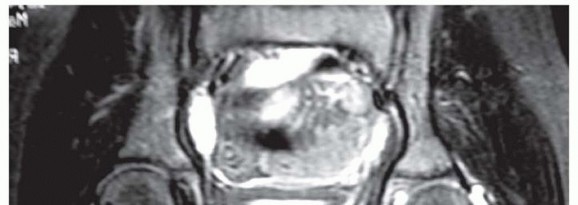

The labral support (shelf) procedure has been used in patients with Legg-Calvé-Perthes disease (or Perthes disease) in Waldenström stages of necrosis or fragmentation in which the femoral head shows deformity or is at risk for deformity6, 12 (

FIG 1

).

FIG 1 • Anteroposterior (AP) radiograph of an arthrogram demonstrates a labral support (shelf) in a patient with Perthes disease. The shelf supports the labrum and enlarges the acetabulum to prevent subluxation of the femoral epiphysis.